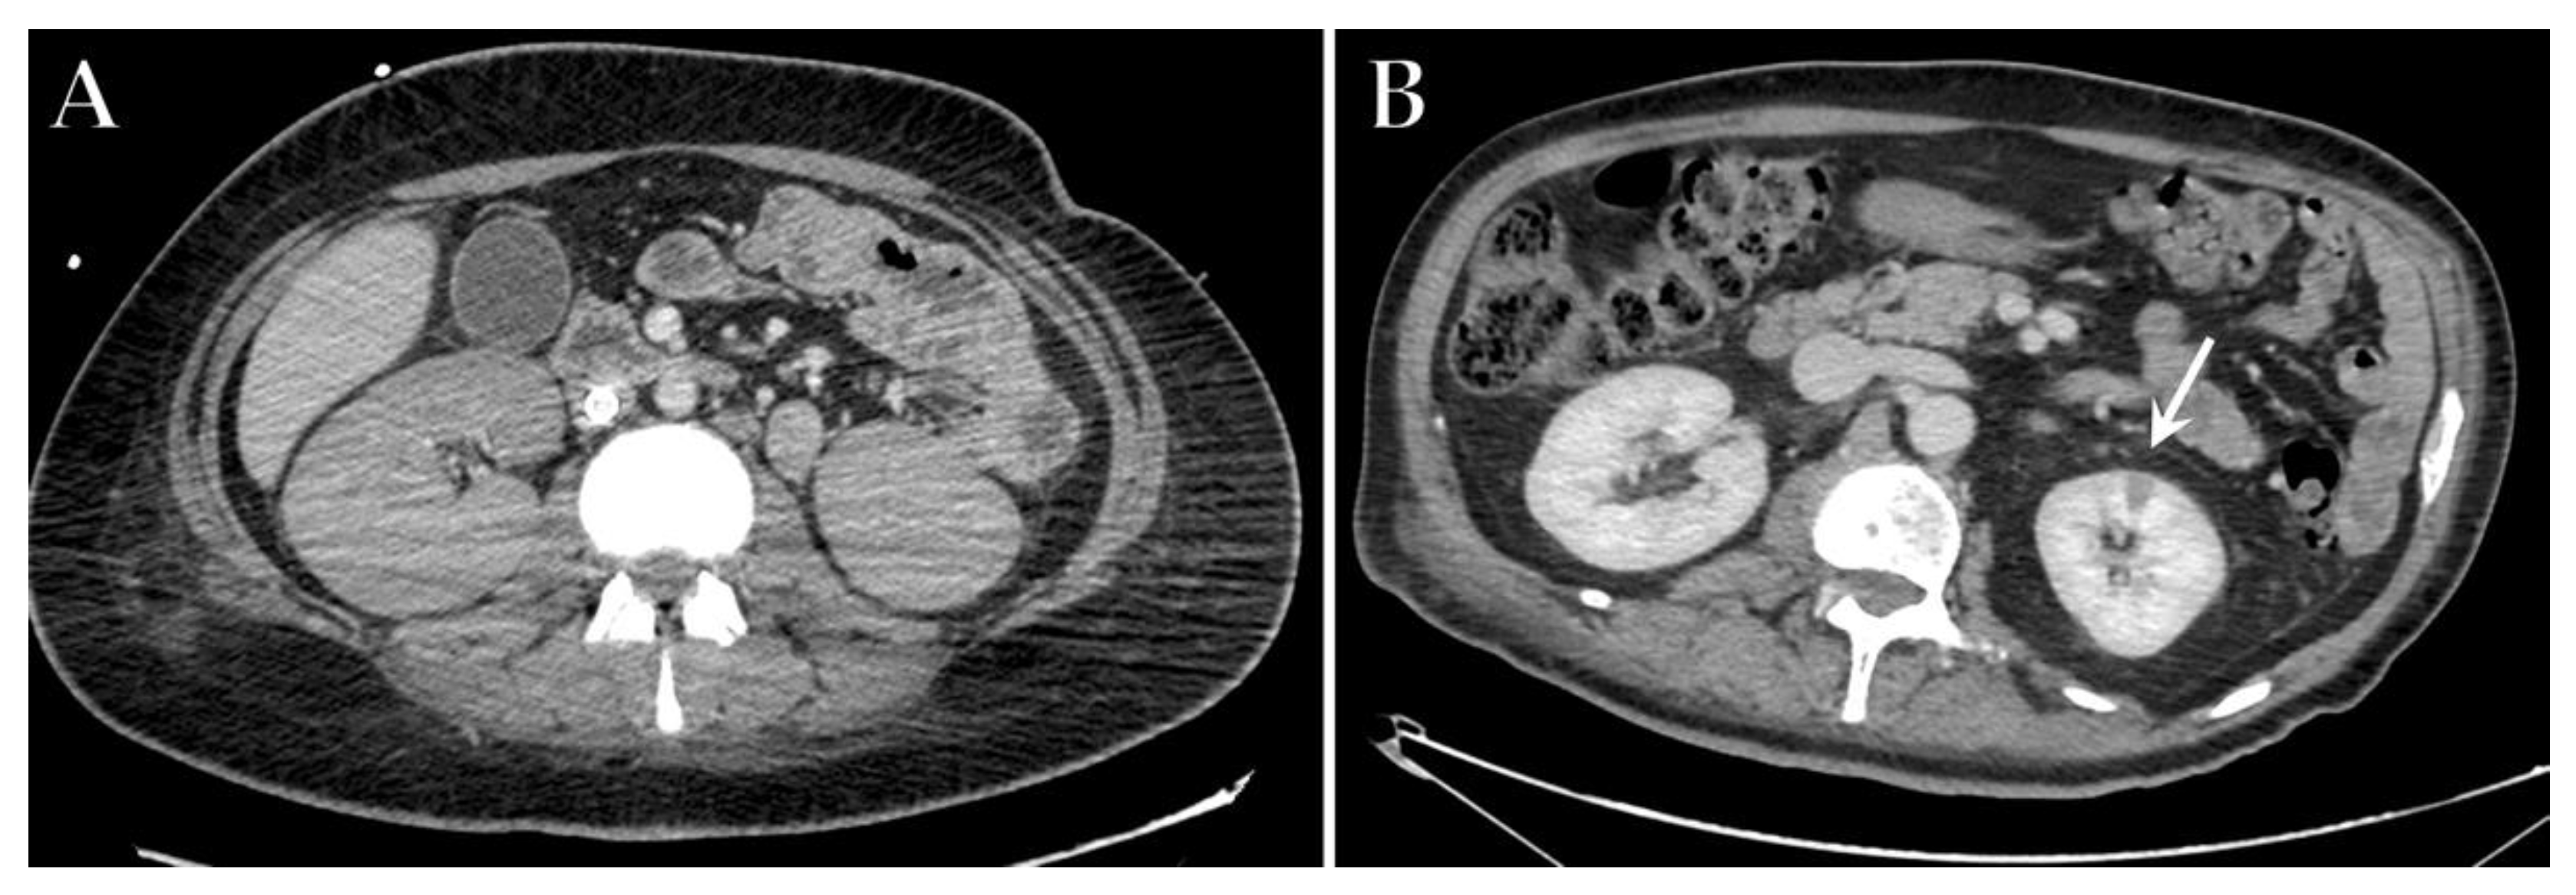

7. Gastrointestinal Complications

8. Renal Complications

- Abdelmohsen, M.A.; Alkandari, B.M.; Razek, A.A.K.A.; Tobar, A.M.; Gupta, V.K.; Elsebaie, N. Abdominal Computed Tomography Angiography and Venography in Evaluation of Hemorrhagic and Thrombotic lesions in Hospitalized COVID-19 patients. Clin. Imaging 2021, 79, 12–19. [Google Scholar] [CrossRef] [PubMed]

- Akin, I.B.; Altay, C.; Kutsoylu, O.E.; Secil, M. Possible radiologic renal signs of COVID-19. Abdom. Radiol. 2021, 46, 692–695. [Google Scholar] [CrossRef] [PubMed]

- Post, A.; den Deurwaarder, E.S.G.; Bakker, S.J.L.; de Haas, R.J.; van Meurs, M.; Gansevoort, R.T.; Berger, S.P. Kidney Infarction in Patients With COVID-19. Am. J. Kidney Dis. 2020, 76, 431–435. [Google Scholar] [CrossRef] [PubMed]